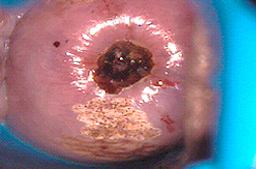

La eletrocauterización de "úlceras del cérvix" sin una colposcopía es un tratamiento que expone a las pacientes a desarrollar un cáncer oculto.

Cuando se utiliza en vagina, vulva y pene puede dar una profundidad mayor de la deseada y ocasionar problemas de cicatrización como se observa en las imágenes, o perforaciones del tejido hacia vejiga y/o recto.